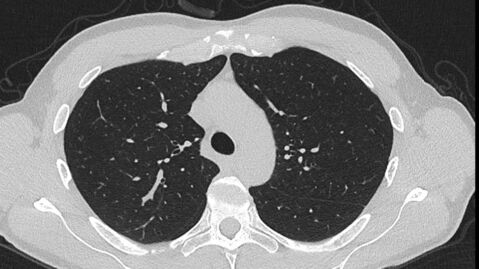

For contrasting purposes, a set of healthy lungs under a CAT scan will show black gaps that are filled with air as it is intended to be.